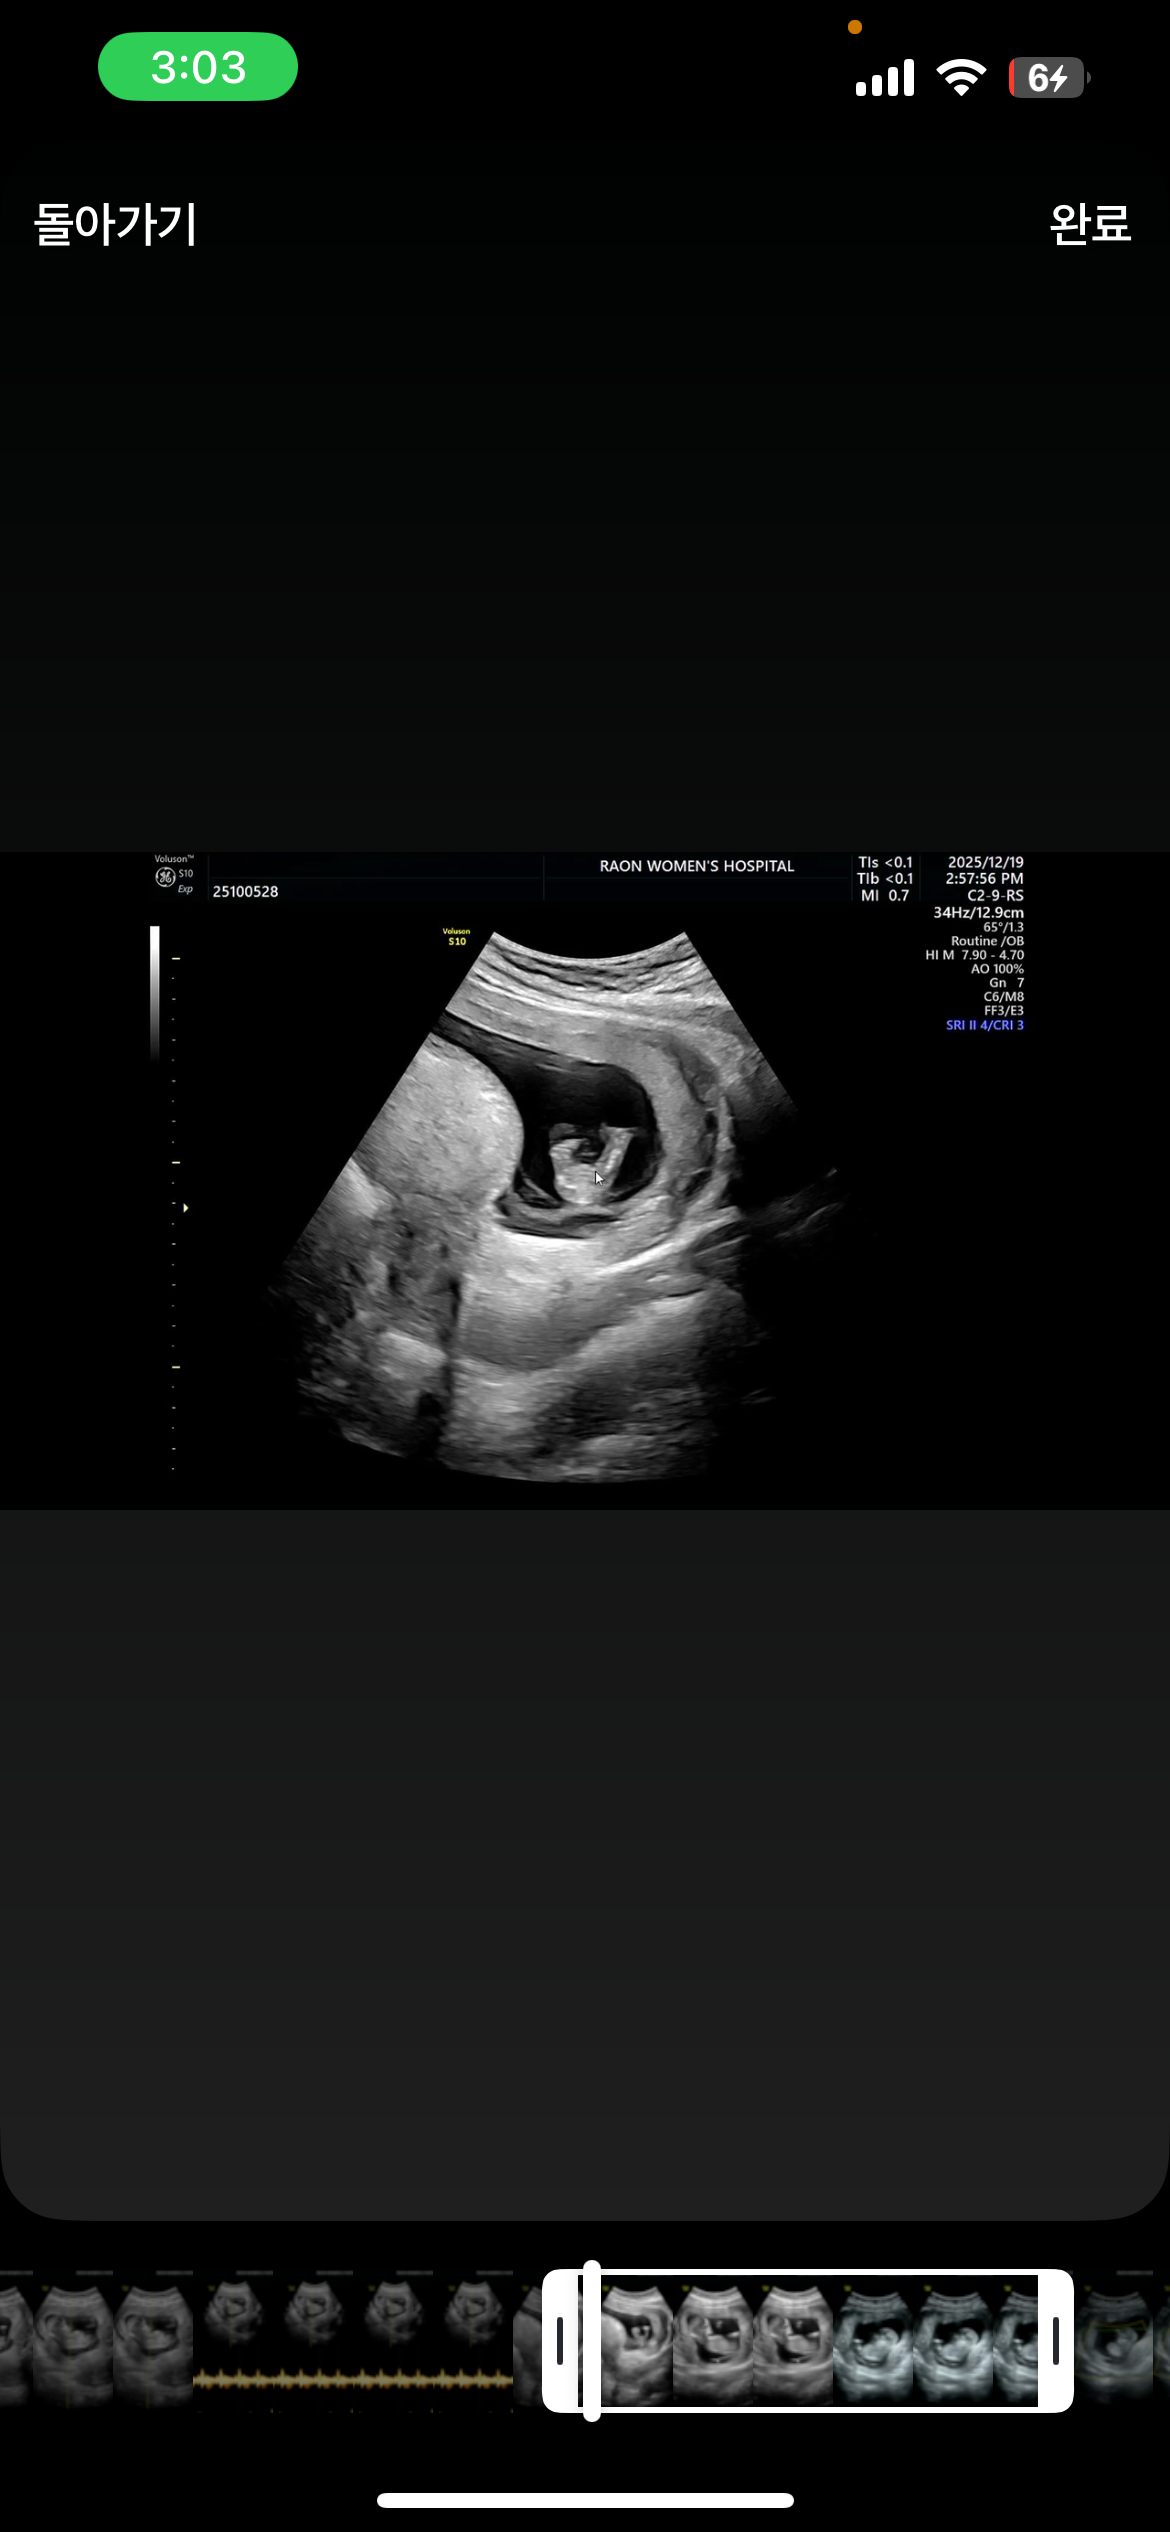

너무 이르지만 성별을 벌써부터 기대하고있는 초보맘입니다🙏🏻 딸이였으면,, 딸이였으면,,, 하는데 오늘 찍은걸 보니 내적 기대치가 Max ,,,, 다른분들이 보는 각도법/ 심장소리차이 (들어도모름) 으로는 모르겠어서 마음만 기대해봅니다,,

심장소리는 미신 수준이고요 각도법은 12주차부터 알 수 있는데 몇가지 조건이 잘 맞아야 돼요 척추 또는 허벅지/다리랑 생식기 간의 각도를 보는거라 옆모습에 다리랑 생식기가 잘 나와야해요! 물론 이또한 정확도가 높긴해도 100%까진 아니예요~